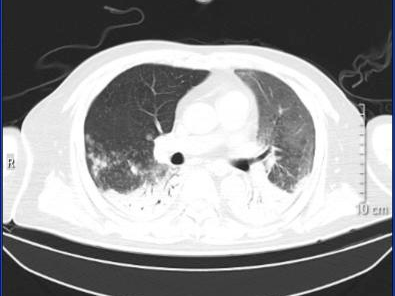

案例1:

一位孕晚期女性,因“发热4天、咳嗽1天”由外院转入该院ICU。初期在外院按流感进行了抗病毒治疗,但效果欠佳。转入ICU时已出现血压低、心率快、呼吸急促等休克表现。完善CT检查发现半个肺“全白了”,后经检测确诊为“鹦鹉热”,经针对性治疗后,这位孕妈已好转出院。

图片

治疗前

治疗后